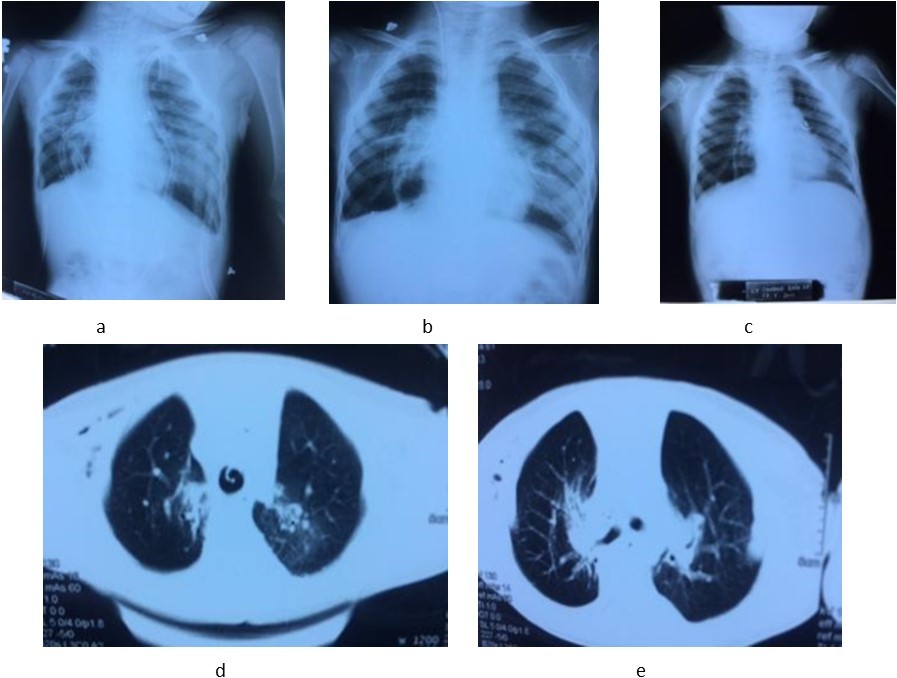

Early outcome: After the operation, the patient was ventilated via endotrachial tube, controlled the status of respiration, hemodynamics and draignage care. Recipient was weaned off ventilator in 36 hours. Postoperative immunosuppression consists of triple drug therapy with neoral, cellcep, and prednisolone. We judge acute rejection on the clinical, radiographic fndings, other subclinical tests and control opportunistic infection. At 1, 3, 6, 9 and 12 months after LDLT, the recipient has recovered lung function very fast and there were not any early complications and adverse events after the operation. Now the recipient had normal physical exercise capacity, subclinical tests in normal limits and not respiratory symptoms, opportunistic infection and no evidence of rejection. (Image 2)

Image 2.The chest X-ray images at the first (a), 7th day (b) and 12th month (c). CT-scan images at the 3th day (d) and 8th day (e) after lung transplantation.

In recent years, the number of lung transplantation patients has increased remarkbly with the trend to bilateral lung transplantation more than single lung transplantation. The sources of donors are extended, with non-heart beating donors, ex-vivo lung perfusion and living donors. LDLT is a last option chosen to save critically ill patient with end-stage pulmonary disease who cannot wait for organs from cadaveric donor4. In our receipient, the indication of lung transplantation was resonable because he always had recurent respiratory infection, decreased PaO2, increased oxygen requirements, hypercapnia, pulmonary arterial hypertension. Two donors were relative and young. The anatomic and functional size matchings between the receipient and two donors played a very important role in the success of this lung transplantation case. We use a formula to estimate graft FVC (Forced vital capacity) on the basis of the donor’s measured FVC and the number of pulmonary segments being implanted4. The right lower lobe FVC of uncle estimated 0.71 (L), the left lower lobe FVC of father estimated 0.8 (L), the receipient FVC estimated 0.98 (L). Total FVC of the two grafs/ FVC of the recipient was 1.5 (according to the Japanese authors, it is acceptable when this ratio > 0.45). Therefore, after vetilation these 2 lung lobes expanded nearly completly with the size of the paient’s chest cavity and by the 7th day, both 2 lung lobes had expanded completly. At the 1st, 3th, 6th , 9th and 12th month, the chest X-ray image are normal. The clinical change of the recipient: fever immediately after operation and recovered in 2 days, sputum in 5 days, oxygen therapy in 5 days; weaned off ventilator in 36 hours. After 4 days, he was withdrawn from thoracic drainage and could walk himself in the room at the 6th day after the operation. In the 1st, 3th, 6th, 9th and 12th month, he had normal physical activities, not any clinical symptoms (now he returns to school and takes part in all activities as his classmates), subclinical tests in normal limits and no evidence of opportunistic infection or rejection.